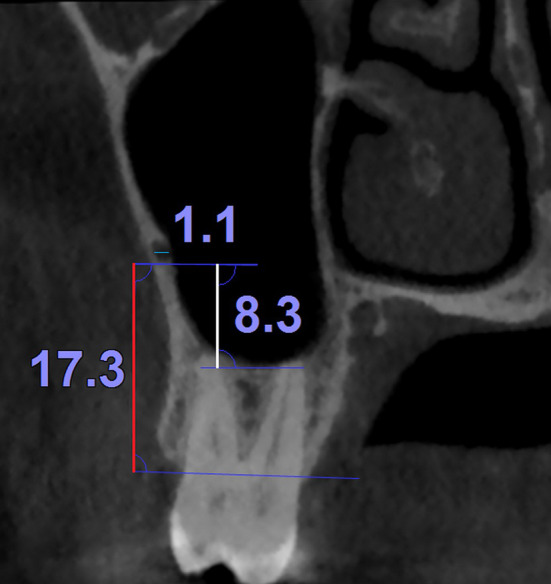

A trained radiologist assessed the presence of PSAA on coronal slices of the lateral wall of maxillary sinus that passed through the premolar and molar areas (four slices per quadrant); these areas were determined by ensuring the presence of radicular apexes of premolars and palatal apexes of molars when the teeth were present. If the area was edentulous, the area was determined based on the distances from the anterior and posterior teeth as well as overall anatomical assessment of the alveolar bone. The following parameters were as well evaluated on each of the four dental areas: (A) The PSAA canal diameter was measured separately in coronal slices. This variable was used both as a continuous parameter and as a variable categorized into three groups: (1) diameters below 1 mm, (2) diameters between 1 and 2 mm, and (3) diameters greater than 2 mm [4]. (B) The vertical distances between the inferior border of the canal with the alveolar crest and (C) the sinus floor [8] were measured as well (Fig. 1).

Fig. 1.

An example of the continuous measurements used in this study (i.e., the distances between the inferior border of the PSAA canal with the alveolar crest and the sinus floor [vertical measurements] as well as the PSAA canal diameter [the short horizontal line]) on a coronal section of the maxilla